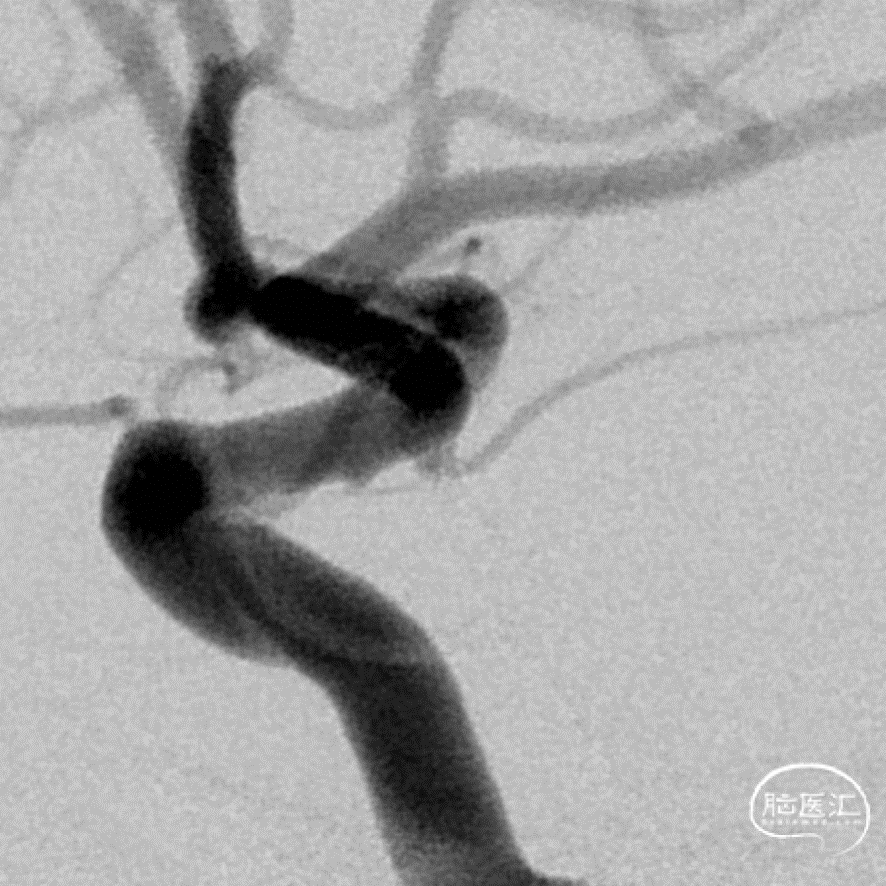

正位造影

侧位造影

DSA三维重建

DSA:数值测量

脉络膜前动脉动脉瘤和真性脉络膜前动脉动脉瘤的鉴别,后者的位置距离脉络膜前动脉和颈内动脉的连接处有一段距离